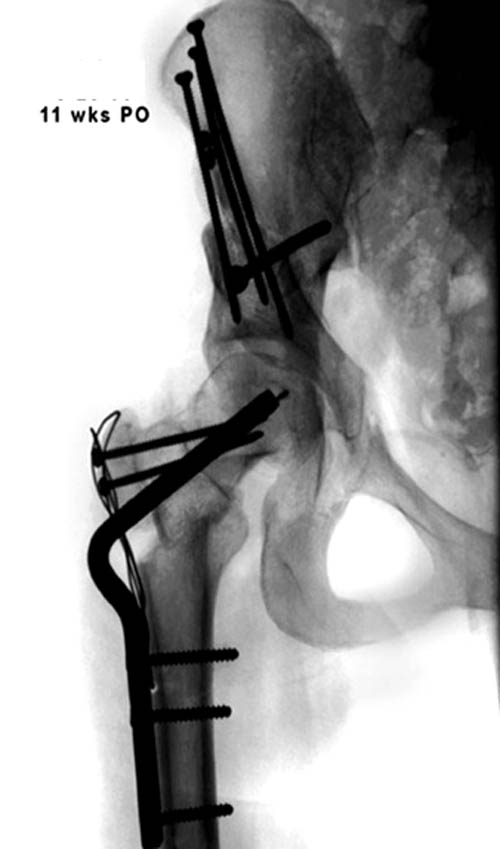

Представленный случай имеет схожесть...., и последний снимок после 2 х лет.